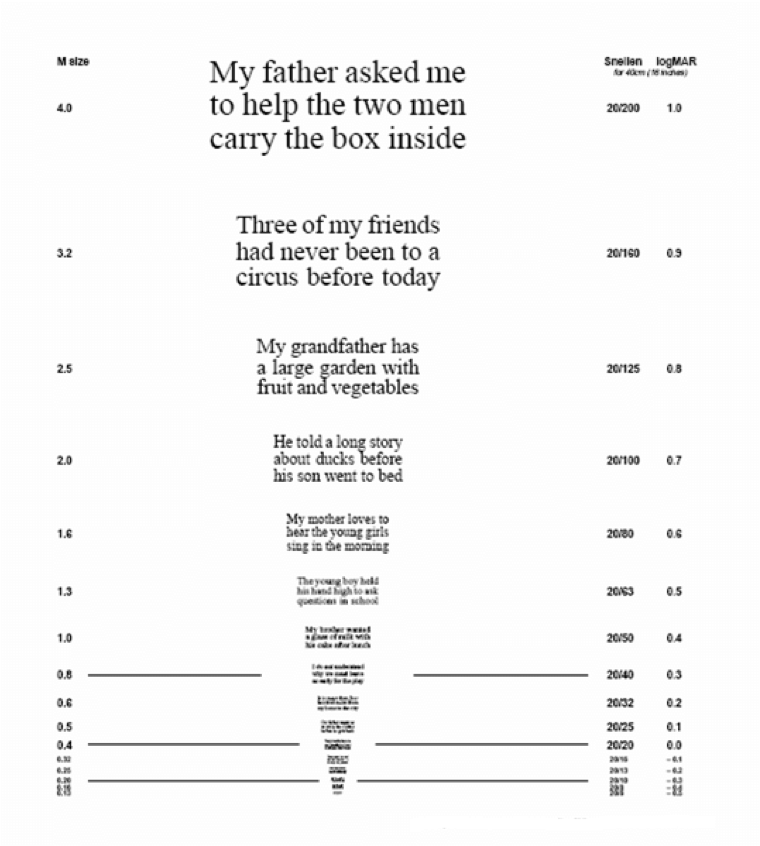

Die MNRead Acuity Chart-Lesetafeln oder Minnesota-Lesetafeln für eingeschränktes Sehvermögen

Im täglichen Leben kann die Vielfalt unterschiedlicher Textgrößen für Menschen mit AMD eine große Herausforderung darstellen, da sie in der Regel Schwierigkeiten haben, eine gute Lesegeschwindigkeit beizubehalten. Die MNRead Acuity Chart-Lesetafeln messen die individuelle Lesegeschwindigkeit in Abhängigkeit von der Schriftgröße. Eine Person liest Sätze in abnehmender Schriftgröße laut von einer Lesetafel ab. Der Punkt, an dem die Lesegeschwindigkeit bei kleinerer Schriftgröße abnimmt, korreliert mit dem Sehvermögen der Person.